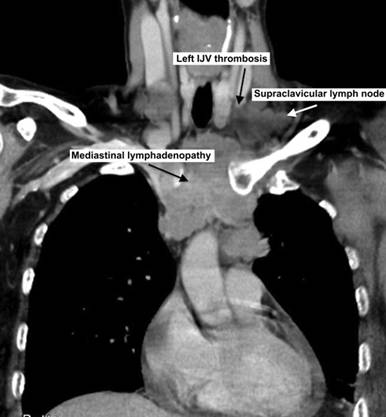

Figure 4. Chest and neck CT showed extensive mediastinal disease, neck lymphadenopathy, left internal jugular thrombosis. IJV: internal jugular vein |

Ultrasound and subsequent computerized tomography (CT) showed no gallstones but CT showed liver lesions which were reported initially as hemangiomas. On the 9th day of admission she developed swollen left upper limb. At that stage the radiology imaging were reviewed at the radiology multidisciplinary team meeting and her chest X-ray was compared to the previous one of two months which showed significant mediastinal widening and chest CT was suggested and showed extensive mediastinal disease and left internal jugular vein thrombosis and compression of left subclavian vein (Figures 1-4). The radiologist suggested lymphoma as the primary malignancy; however, the bone marrow biopsy showed a cellular marrow extensively infiltrated by a high-grade malignant tumour composed of small cells with scanty cytoplasm. Numerous mitoses were seen. Immunocytochemistry demonstrated a strong positive reaction for CD56 and bcl2, while a focal positive reaction was seen for bcl6. Perinuclear dot positivity was seen for MNF116. A negative reaction was seen for CD79, CD20, CD34, CD23, CD10, CD5, CD3 and cyclin D1.